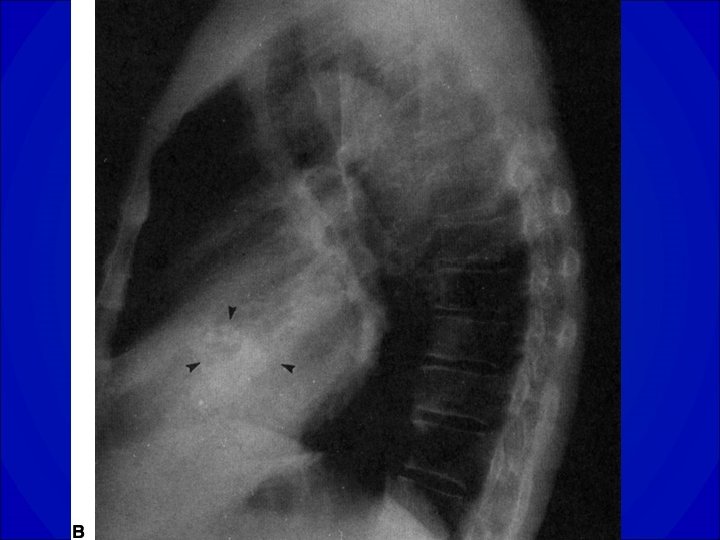

Diagnostic • ECG Hypertrophie VG • Radiographie de thorax= dilatation du VG • Echocardiographie Trans thoracique ++ -Confirmation et quantification de la fuite -Évaluation du retentissement VG -Lésions associées ? Anévrysme de l’aorte ascendante ? • Scanner et /ou IRM étude de l’aorte initiale si difficultés échographiques

Diagnostic • ECG ACFA, Surcharge auriculaire gauche, Signes d’atteintes VG (HVG, Ondes Q…. ) • Radiographie de thorax= dilatation du VG • ETT +/- ETO -Confirmation et quantification de la fuite -Faisabilité d’une réparation chirurgicale (plastie) -Évaluation du retentissement VG -Lésions associées ?